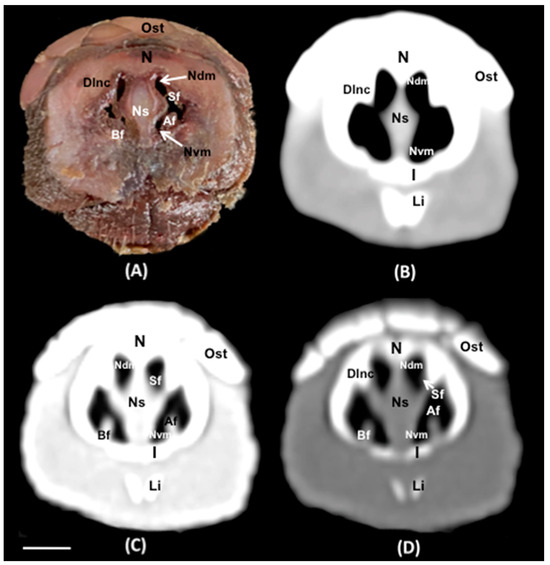

Abstract

3. Results

3.1. Anatomical Sections